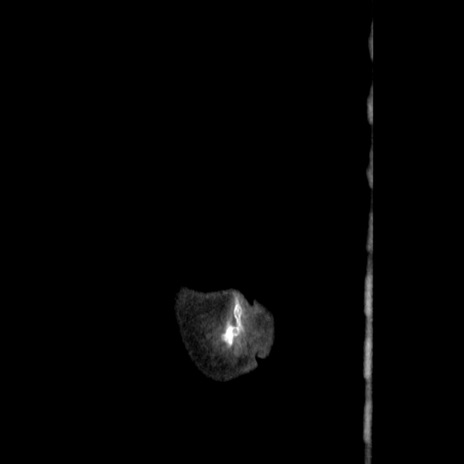

横断像